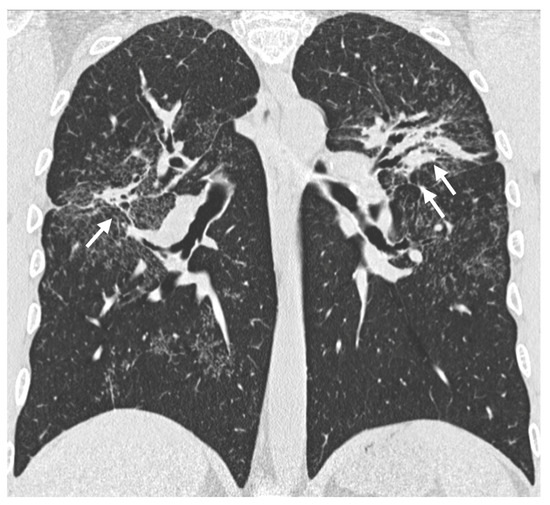

Background: Hypersensitivity pneumonitis (HP) is an interstitial lung disease (ILD) caused by repeated exposure to inhaled antigens in susceptible subjects. High-resolution computed tomography (HRCT) of the lungs is the leading diagnostic method for ILDs, but in some cases HRCT findings are not sufficient to distinguish HP and other ILDs, particularly, fibrotic HP (fHP) and usual interstitial pneumonia (UIP). Objective: The aim of this study was to develop HRCT criteria to diagnose fHP in patients with a UIP-like pattern. Methods: In this retrospective study, we analyzed HRCT scans of patients with fHP and a UIP-like pattern who underwent lung biopsy, and patients with idiopathic pulmonary fibrosis (IPF) and a UIP pattern in HRCT. Results: We included 51 patients with confirmed fHP and 24 patients with IPF/UIP in the analysis. IPF/UIP patients were older, were prevalently males, and did not have any systemic autoimmune diseases or risk factors for other ILDs. fHP patients were younger, with an equal number of males and females, and were more likely to be exposed to environmental antigens. HRCT abnormalities in the fHP group predominated in the lower lung areas or were diffuse in axial scans, whereas IPF/UIP patients mostly demonstrated a diffuse craniocaudal distribution and subpleural axial predominance. Centrilobular nodules and mosaic attenuation were present significantly more often in the fHP group; honeycombing, traction bronchiectasis, and emphysema prevailed in IPF/UIP patients. In the logistic regression analysis, patients with fHP and IPF/UIP differed in the presence of centrilobular nodules, honeycombing, and in both craniocaudal and axial distributions of HRCT abnormalities. In the ROC analysis, the combination of centrilobular nodules, honeycombing, and diffuse axial and craniocaudal distributions can predict the diagnosis of fHP (AUC, 0.953 ± 0.022; 95%CI, 0.910–0.995; p < 0.001). Mosaic attenuation and reticulation did not change the probability of fHP. Conclusions: The most significant HRCT features of fHP compared to the UIP pattern were centrilobular nodules, honeycombing, and a diffuse axial and craniocaudal distribution of abnormal findings. Reticulation, mosaic attenuation, and GGO do not increase the probability of fHP. Full article